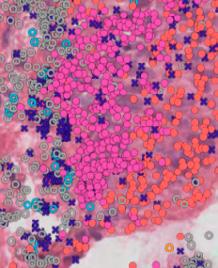

CCI pilot study uses Large Language Model Artificial Intelligence (LLM AI) to automate data extraction

To validate the AI’s performance, the extracted data was compared against a “ground truth” established by expert scientists through manual review. The results were promising: the PDF-to-text conversion was highly accurate, even for handwritten content, and the LLM reliably extracted explicit facts such as test names, dates, and numerical results.